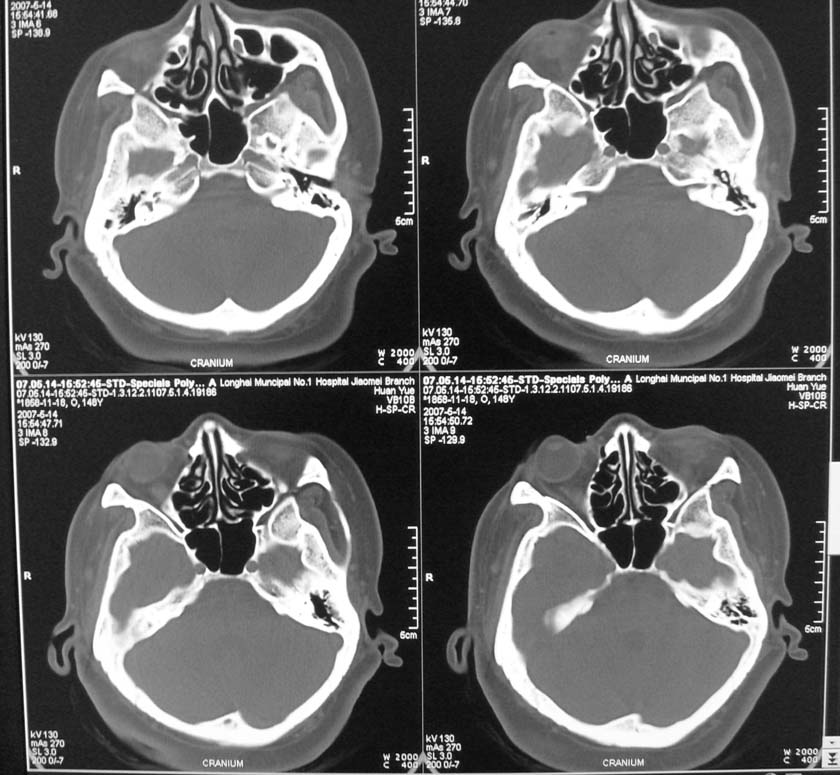

以下是引用天南地北在2007-5-15 23:30:00的发言:[br]看不出来什么[br]建议冠面增强扫描,或mri检查

以下是引用郭凯在2007-5-16 0:17:00的发言:[br]看不到,如果临床支持的话还是做mri看一下吧,对垂体微腺瘤比较敏感.[br]ct上看不到不能乱报.

以下是引用jiangjing在2007-5-16 11:06:00的发言:[br]看不出来什么[br]建议冠面增强扫描,或mri检查